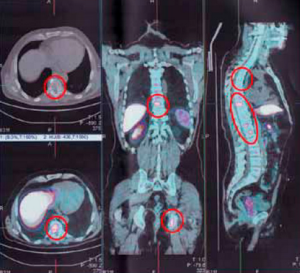

Metastazele în prognoza coloanei vertebrale, fotografii, șansele

Coloana vertebrala este cel mai frecvent site pentru metastaze. Metastazele la nivelul coloanei vertebrale - o tumora secundara, ceea ce înseamnă că procesul de cancer a început în alte părți ale corpului. Mai mult de 90% din leziunile canceroase ale spatelui si a coloanei vertebrale sunt formațiuni metastatice.

Pentru tratamentul general, este esențială pentru un diagnostic precis și recunoașterea corespunzătoare a naturii cancerului primar, numărul de leziuni, prezența metastazelor osoase la distanță, precum și de compresie a maduvei spinarii.